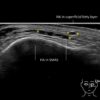

Filler deposits may end up unintentionally in the SMAS or fascial layers of the skin. Very often this will not lead to adverse events, however, adverse events ( nodules, migration / redistribution impaired muscle movement and smiling and malar edema) are are often related to filler ending up in the SMAS or fascia.

Study the first image to recognize the different layers. If you are sure about the layers, swipe to the second image to view the answer (if applicable).